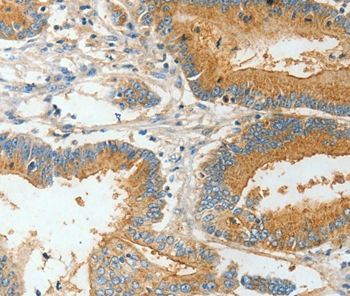

Immunohistochemical analysis of paraffin-embedded Human colon cancer tissue using #36274 at dilution 1/30.